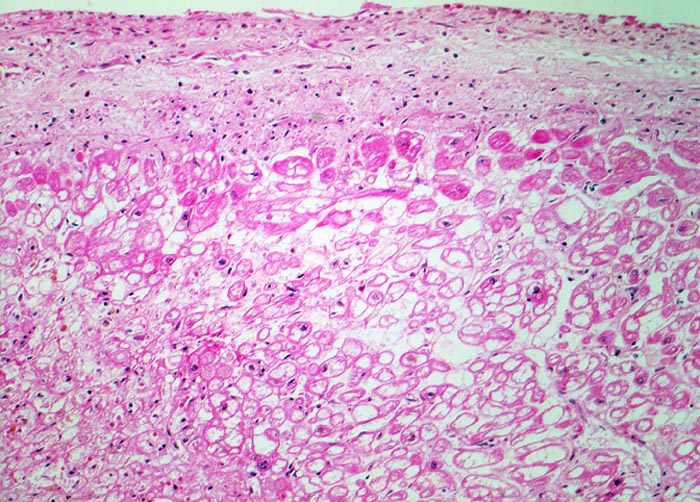

Die unmittelbar subendokardial gelegenen Herzmuskelzellen des Papillarmuskels sind vital (erhaltene Zellkerne), zeigen aber ein blasig vakuolisiertes und aufgehelltes Sarkoplasma (=tubuläre Degeneration) als Zeichen eines chronischen Sauerstoffmangels (sogenannte Holundermarkzellen).